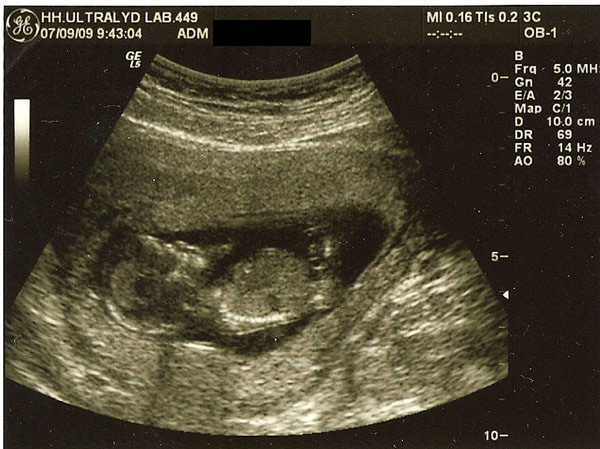

De første 2 billeder er fra nakkefoldescanningen (i uge 13), det næste er fra misdannelses scanningen i uge 20 og det sidste (og dårligeste) er fra den første hjerte scanning i uge 26.